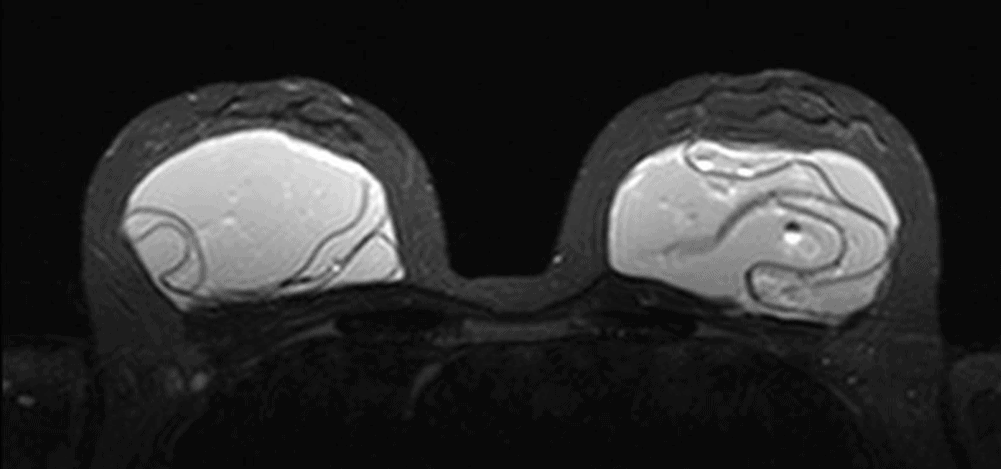

Breast implant ruptured